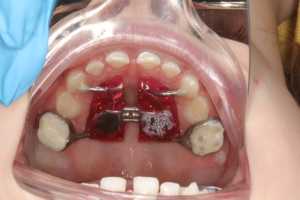

Классический аппарат состоит из винта хайрекс, пластмассового базиса, опорный колец на молочные моляры и направляющих к молочным к клыкам.

Но, конечно же, в зависимости от клинических ситуаций могут быть индивидуальные модификации. Например, при преждевременном удалении молочных зубов. В таких случаях опорные кольца изготавливаются на постоянные шестые зубы.

Аппарат Хааса состоит из колец на первые постоянные моляры или вторые молочные моляры и дополнительных лапок на молочные клыки или колец на первые премоляры, а так же имеет пластмассовый базис с винтом Hyrex, который плотно прилегает к слизистой оболочке неба.

Как подкручивать аппарат Хааса? - для этого есть специальный ключ, которым родители самостоятельно активируют аппарат по схеме доктора.

Первая активация обычно самая сложная для родителей, поэтому я напишу несколько рекомендация по активации аппарата:

1. Посадите ребенка или можно положить на кровать

2. Настройте освещение — можно фонарик или настольную лампу, чтобы хорошо увидеть аппарат и место постановки ключа.

3. Необходимо найти винт и паз — дырочку, которая находится ближе к вам.

4. Вставьте туда ключ, проверьте, что он хорошо там фиксируется

5. Придерживая пластмассовый базис аппарата пальцами второй руки, прокрутите ключ до упора в сторону неба

6. При полной активации вы должны увидеть новый паз

7. Аккуратно достаньте ключ в направлении неба. В этот момент главное - не скрутить винт обратно. Это может произойти, если вы не достали ключ из паза и начали вынимать из полости рта.

Чаще всего аппарат Хааса применяется в детской ортодонтии. Именно в данном возрасте мы можем влиять на рост челюстей, тем самым создавая место для постоянных зубов и корректируя прикус. Дети могут самостоятельно выбрать любимый цвет и картинку для аппарата. Результаты лечения более стабильны и прогнозируемы. Однако аппарат Хааса может применяться во взрослом возрасте. Так как костные структуры уже все сформированы, использование этого аппарата возможно только совместно с хирургически-ассоциированным послаблением небного шва. Показания к применению такие же, как и в детском возрасте. В результате, пациент получит широкую красивую улыбку.